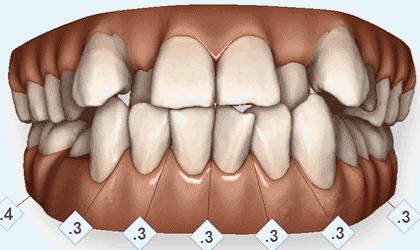

牙齿情况:深覆盖深覆颌

矫正前

牙列不齐,并有牙龈炎、牙结石,刷牙时会出血,同时美观度较差,影响容貌。